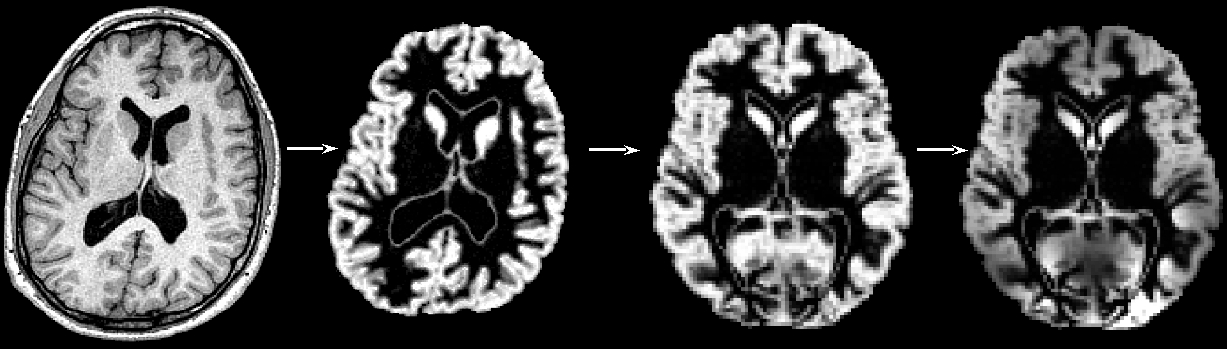

First, all brain-extracted images are segmented into GM, WM and CSF. Then, GM images selected in the template_list file (*_struc_GM) are affine-registered to the GM ICBM-152 template, concatenated and averaged. This averaged image is then flipped along the x-axis and the two mirror images then re-averaged to obtain a first-pass, study-specific "affine" GM template ("template_GM_init"). Second, the template_list GM images are re-registered to this "affine" GM template using non-linear registration, concatenated into a 4D image called "template_4D_GM", averaged, flipped along the x-axis. Both mirror images are then averaged to create the final symmetric, study-specific "non-linear" GM template at 2x2x2mm3 resolution in standard space.

"Structural data was analysed with FSL-VBM (Douaud et al., 2007, http://fsl.fmrib.ox.ac.uk/fsl/fslwiki/FSLVBM), an optimised VBM protocol (Good et al., 2001) carried out with FSL tools (Smith et al., 2004). First, structural images were brain-extracted and grey matter-segmented before being registered to the MNI 152 standard space using non-linear registration (Andersson et al., 2007). The resulting images were averaged and flipped along the x-axis to create a left-right symmetric, study-specific grey matter template. Second, all native grey matter images were non-linearly registered to this study-specific template and "modulated" to correct for local expansion (or contraction) due to the non-linear component of the spatial transformation. The modulated grey matter images were then smoothed with an isotropic Gaussian kernel with a sigma of ?? mm. Finally, voxelwise GLM was applied using permutation-based non-parametric testing, correcting for multiple comparisons across space."